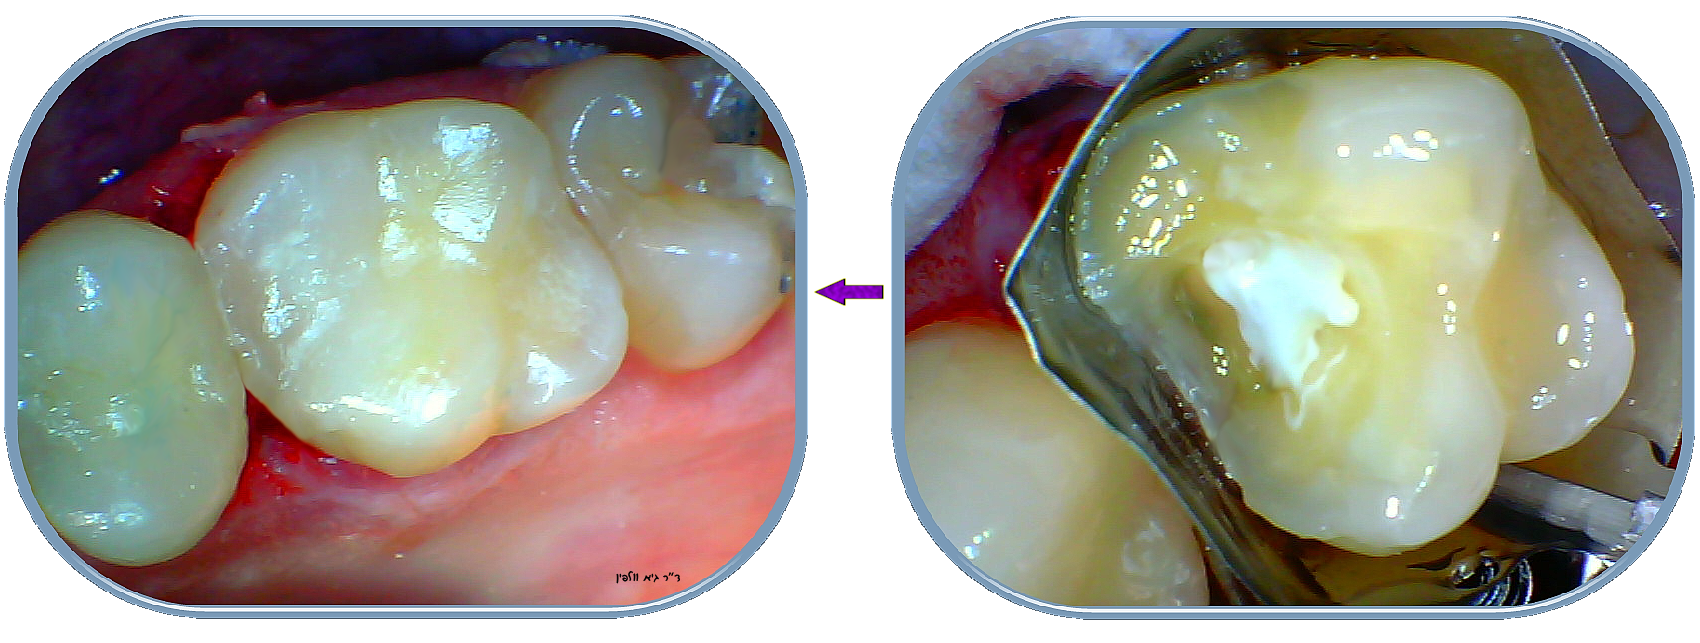

רק לאחר ביצוע כיפוי המוך ימשיך הרופא ויבצע את שיחזור השן והאנטומיה המקורית. כיפוי המוך הנ"ל משפר את הסיכוי של הצלחת הסתימה, לעומת סתימה "רגילה" עמוקה וללא כיפוי מוך. כמובן כל זאת בתנאי שעדיין לא מתפתח דלקת בעצב, נמק או זיהום.

ייתכן ובגין הקירבה לעצב של החור העמוק השן תהיה רגישה בהתחלה לאחר הטיפול, במיוחד לקור ו/או לעיסה של מאכל נוקשה, אך אם אין כאבים קשים שמתפתחים – סביר להניח שהרופא הצליח למנוע את הדלקת בעצב ואת הצורך בטיפול שורש, והרגישות במשך הזמן תפחת. יש לזכור שכל פצע עמוק בגוף מחלים לאט, ובמיוחד בשיניים דרושה סבלנות…